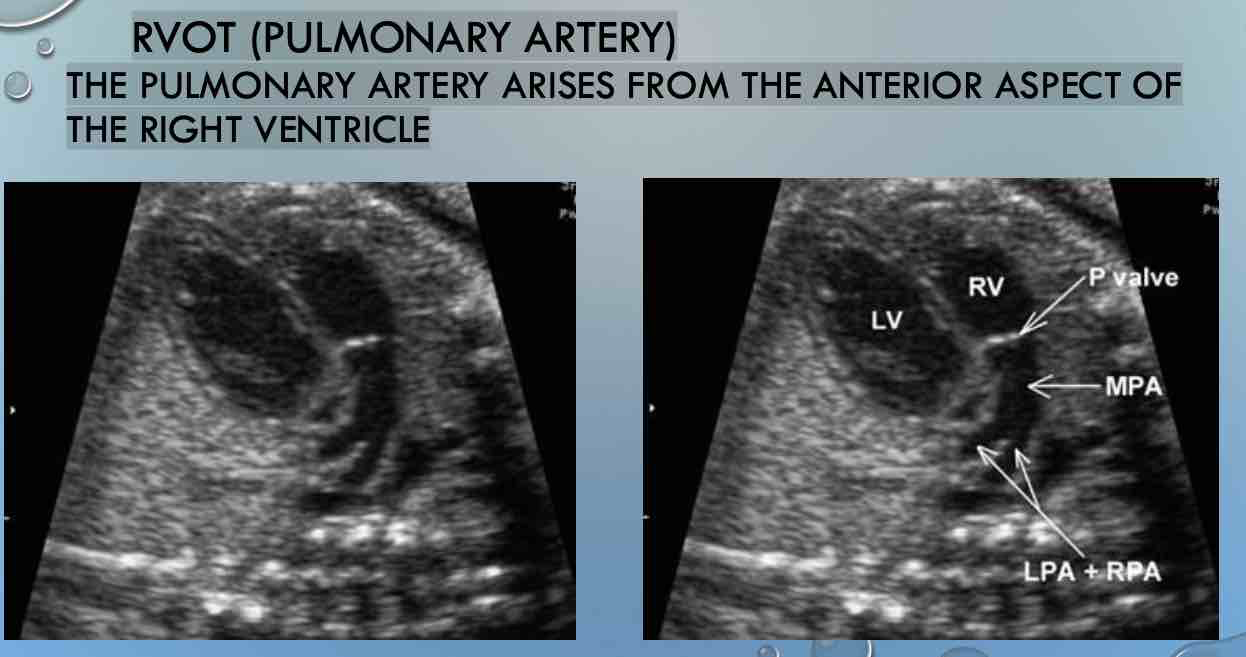

Q

Image 4:

what can you see in RVOT

RVOT (PULMONARY ARTERY)

THE PULMONARY ARTERY ARISES FROM THE ANTERIOR ASPECT OF

THE RIGHT VENTRICLE